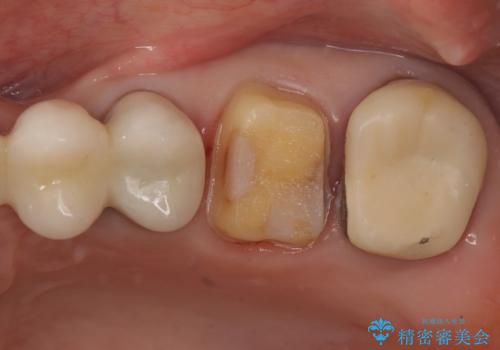

しかし向かい合わせになる歯の咬みこみが強く、インレーでは破折してしまうリスクが高いと予想し、より強固なクラウンで修復することになりました。

向かい合わせの歯の咬みこみが強くインレーよりも強度の高いクラウンでの治療となりました。その中でも色が白くある程度の薄さでも耐久性を発揮するフルジルコニアクラウンでの修復を行いました。適合も良く色調もとてもなじんだため大変喜んでいただけました。